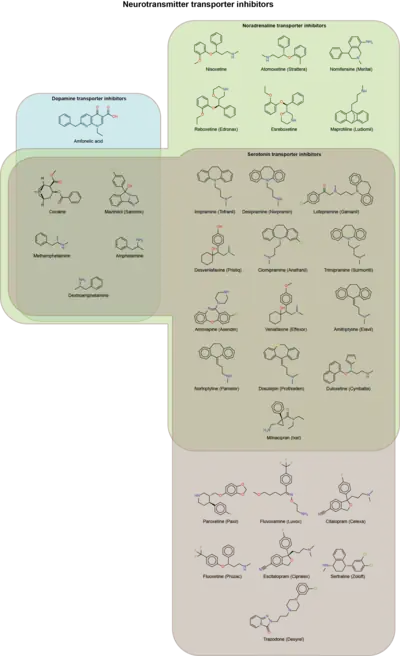

A variety of neurotransmitter reuptake transporters are pharmacotherapeutic targets for modulating the synaptic neurotransmitter concentration, and therefore neurotransmission.

- Antidepressants such as SSRIs, SNRIs and TCAs suppress the activity of serotonin and/or norepinephrine transporters, preventing the reuptake of targeted neurotransmitters from the synaptic cleft.

- Psychostimulants like cocaine, amphetamines, and methylphenidate act by inhibiting and/or reversing the dopamine and/or norepinephrine transporters. Some dissociatives like phencyclidine and ketamine are also dopamine transporter inhibitors.

- Tiagabine, a drug used as an anticonvulsant, acts by inhibiting the GABA transporter 1.